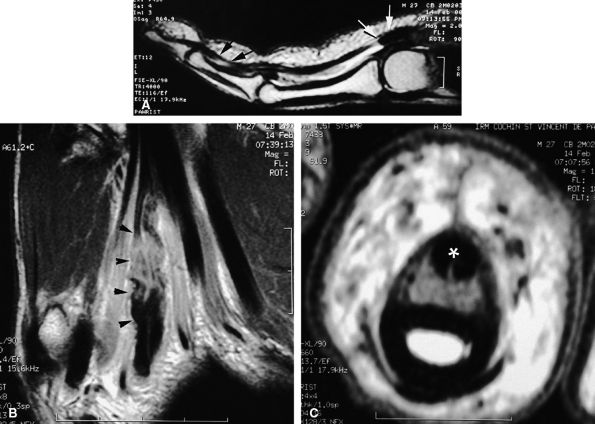

FIGURE 11.34 ● Complete rupture of the central slip of the extensor tendon on sagittal (A) and axial post-enhanced T1-weighted images at the level of the PIP joint space (B) and the distal third of the proximal phalanx (C). There is distal avulsion of the central slip with a tendon gap (arrows) and limited retraction. The proximal end is thickened and shows signal heterogeneity (asterisk).